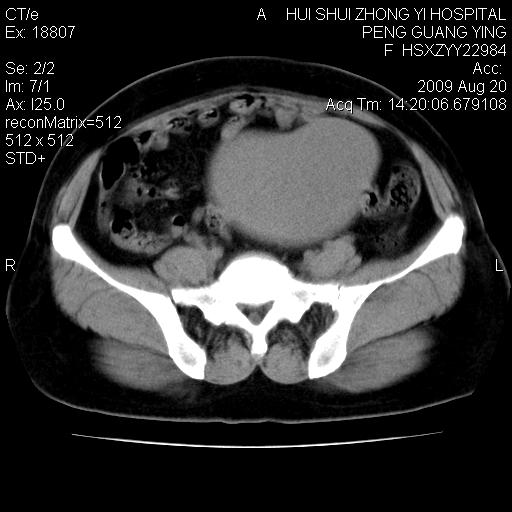

标题: CT21707:女,42岁,因发现下腹部包块2月。 [打印本页]

标题: CT21707:女,42岁,因发现下腹部包块2月。

卵巢囊腺瘤。

考虑 1 卵巢囊腺瘤 2 子宫肌瘤。

目前的影像表现显示肿块位于腹腔及盆腔,但具体定位,分清来源较困难,是否来源于卵巢、子宫无法定论,子宫直肠及子宫膀胱周围脂肪间隙尚较清晰,如果患者有过腹腔好或者盆腔手术史,也可以形成不典型的血中,最好手术后定为定性,我期待结果。

软组织密度,与子宫一致。双侧卵巢形态、密度好,不支持来源于卵巢。

来源卵巢--畸胎类肿瘤

病史不全面,病灶来源可能是子宫或卵巢,若临床有剖腹产、痛经史,则更支持前者,亦更支持子宫腺肌症